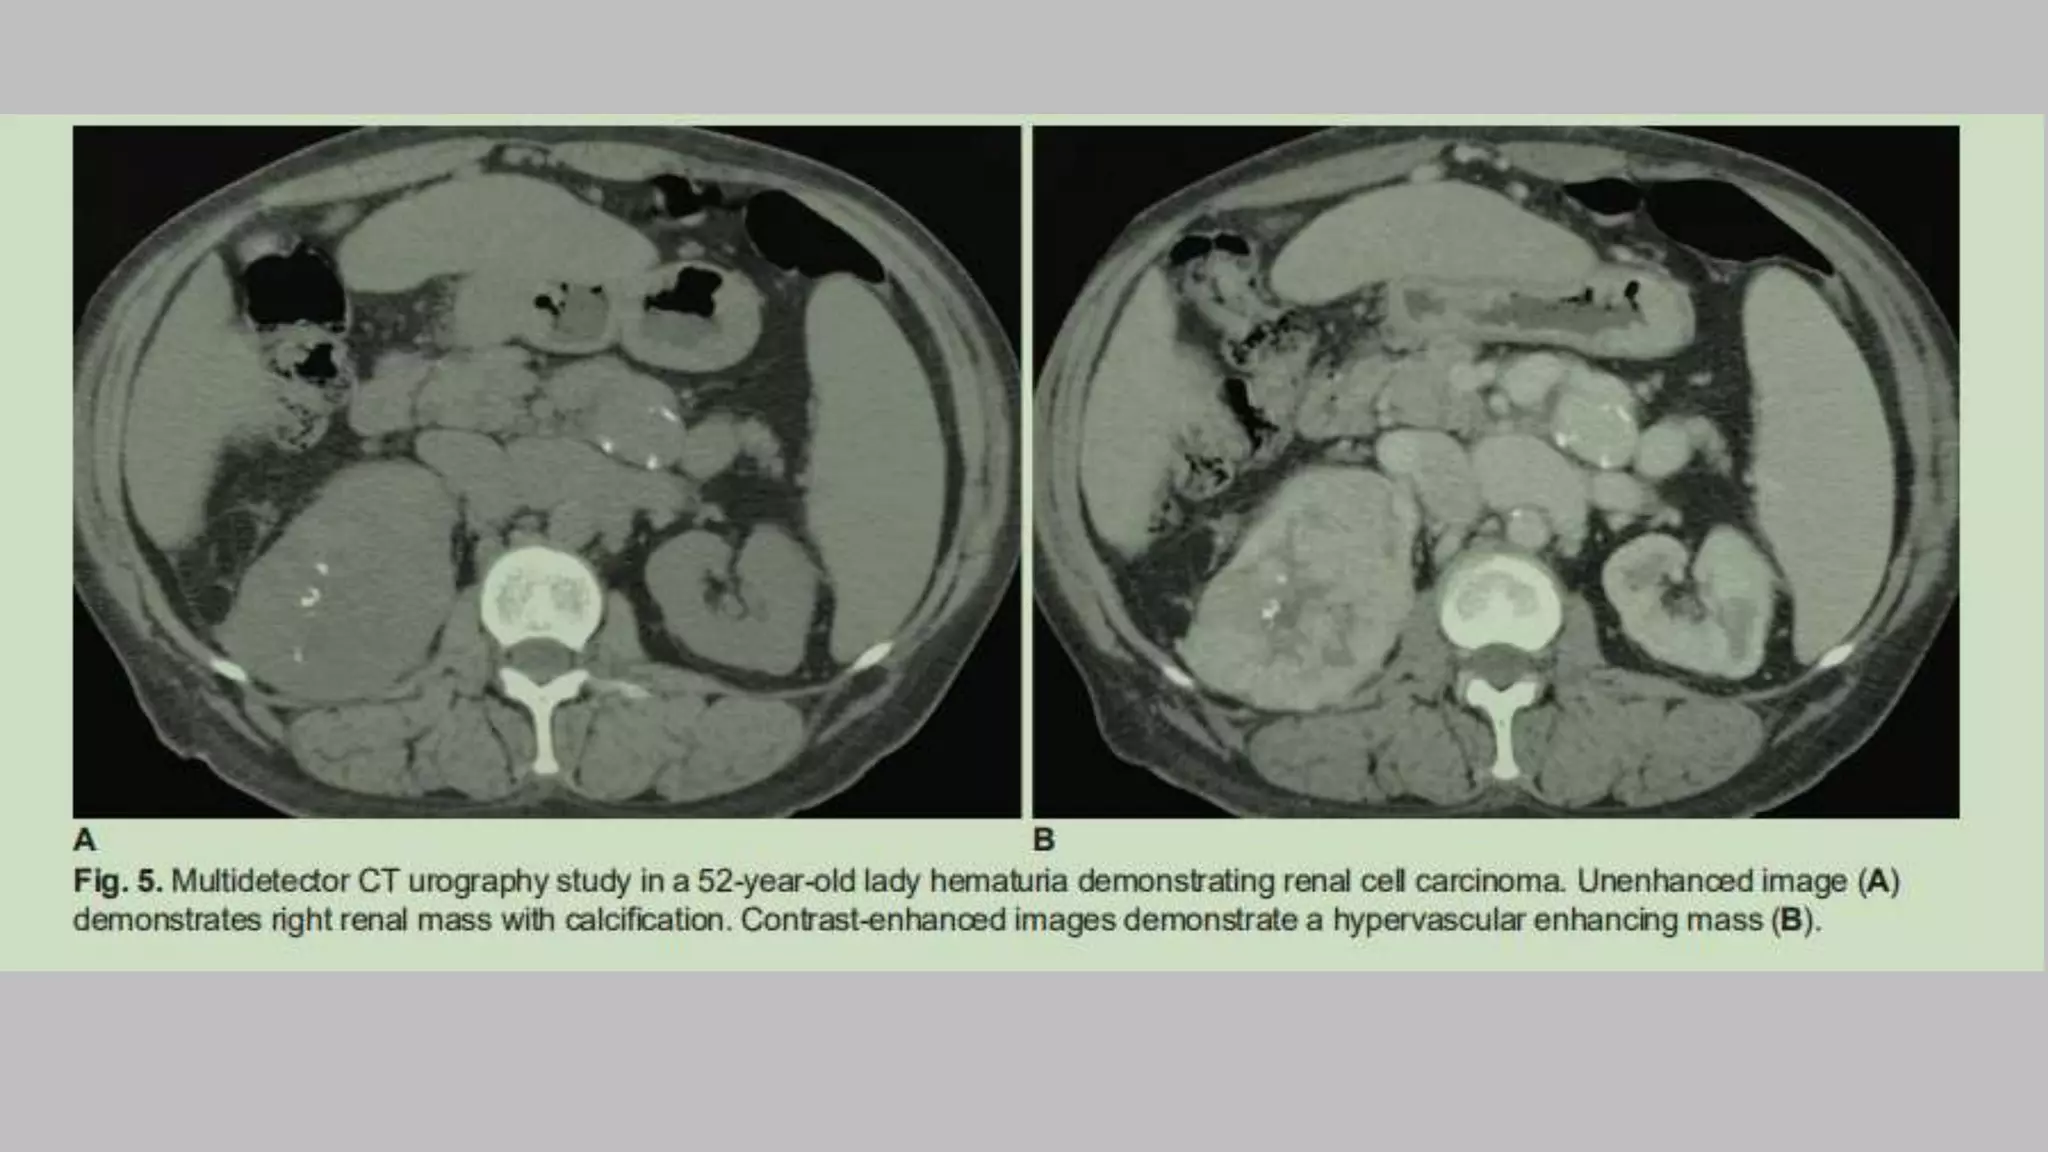

• Malignant urologic tumors, such as renal cell carcinoma and transitional cell

carcinoma, are potentially detectable during unenhanced imaging examinations.

• Renal cell carcinoma and transitional cell carcinoma typically appear solid on

unenhanced images and have higher attenuation (5–30 HU) than urine